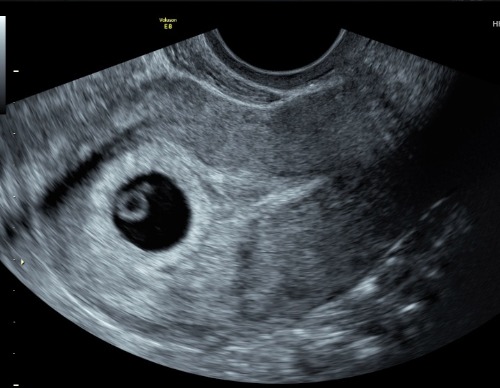

Een lege vruchtzak, ook wel bekend als een ‘blighted ovum’’, kan ontstaan aan het begin van de zwangerschap. Na de bevruchting, begint de bevruchte eicel zich te delen en vormt een groep cellen die uiteindelijk je kindje zal worden. Tegelijkertijd ontwikkelt zich een structuur genaamd de vruchtzak. Soms gaat echter iets mis in dit proces en ontwikkelt je kindje zich niet, terwijl de vruchtzak en de placenta dat wel doen. De vruchtzak blijft dan leeg wat op een echo te zien is.

Een lege vruchtzak kan worden gediagnosticeerd tijdens een vroege zwangerschapsecho, meestal rond de 7-10 weken. Op de echo ziet de arts dan een vruchtzak en mogelijk ook een placenta, maar er is geen teken van een embryo.